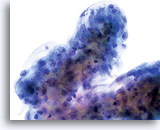

Konventioneller Pap-Abstrich

Adenokarzinom

Konventioneller Pap-Abstrich

Adenokarzinom